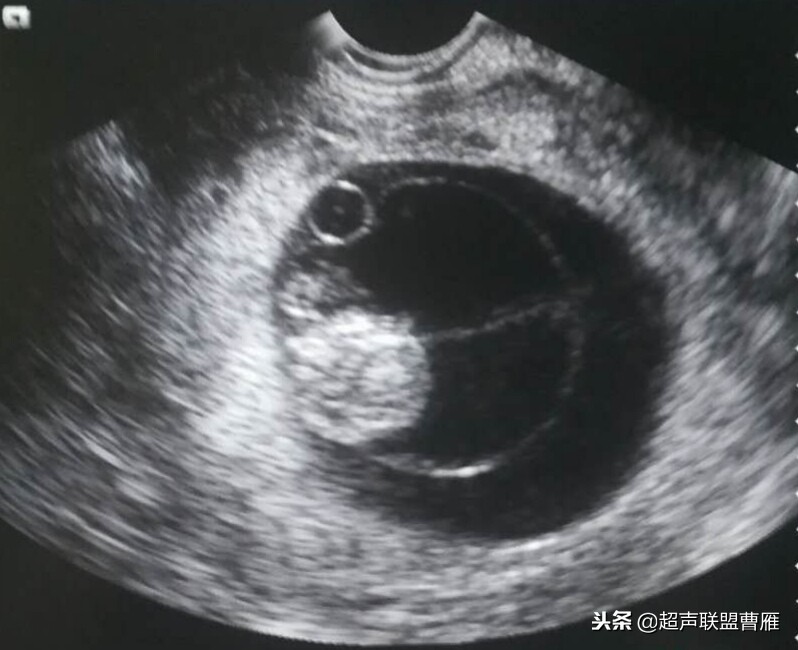

正常早孕卵黄囊声像图

早孕 胚芽 卵黄囊

5周+ 、6周+ 声像图

孕7周左右(胚芽11mm 卵黄囊)

胎芽 卵黄囊 心管搏动信号

宫内早孕 (7周左右)

正常宫内胚胎组织、卵黄囊